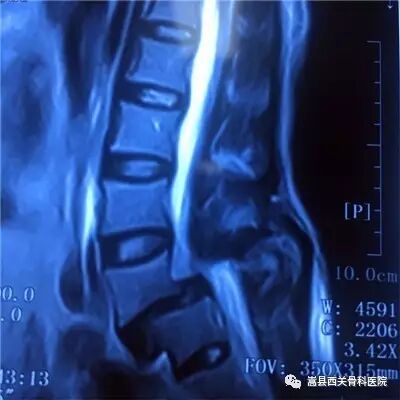

腰椎管狭窄影像资料

腰椎间盘的退变,椎体的骨质增生,后方小关节突的增生,黄韧带的肥厚,椎体滑脱都是造成椎管狭窄的主要原因!